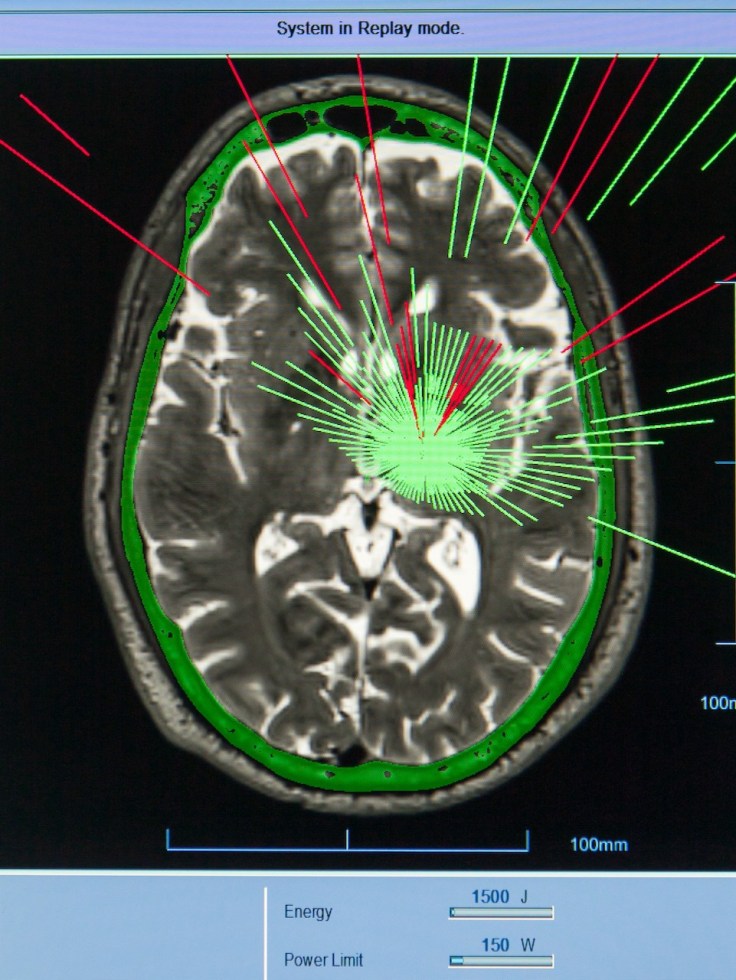

– El procedimiento, guiado por resonancia magnética, dirige ondas ultrasónicas a puntos específicos del cerebro, desactivando las zonas responsables de los temblores sin necesidad de abrir el cráneo.

– La clave del HIFU está en su precisión: se aplica directamente en el tálamo y el subtálamo, estructuras cerebrales asociadas al control del movimiento. Esta intervención permite una mejora visible y sostenida, incluso en pacientes que no respondieron bien a los medicamentos o que no eran candidatos para cirugía.